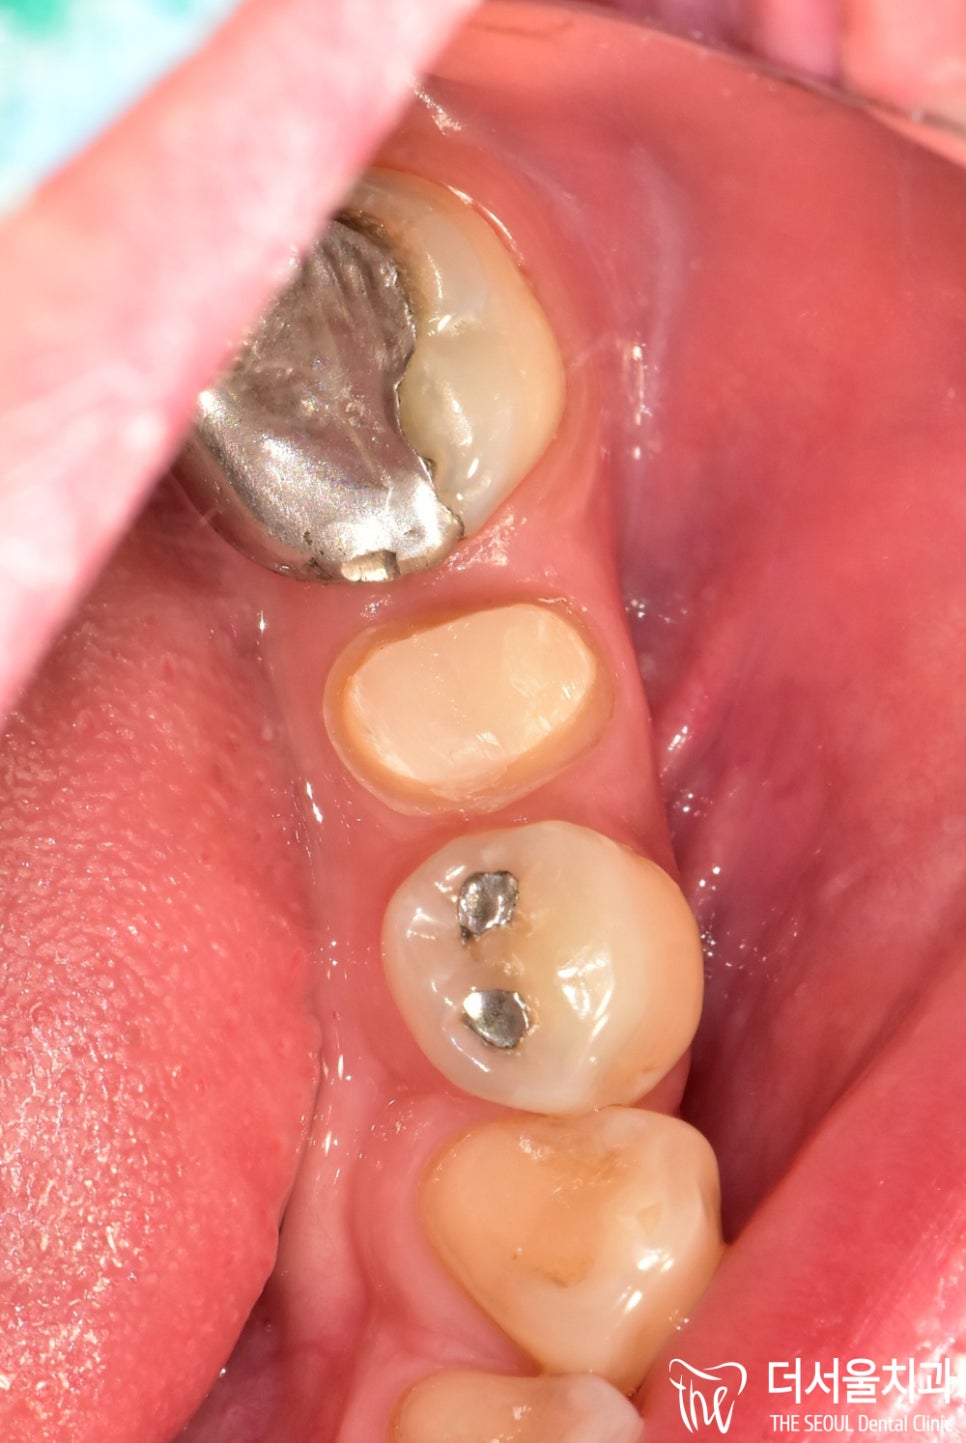

육안으로 살펴본 결과,

통증을 느끼고 있던 작은 어금니를 비롯해

인접한 치아에도 아말감이 씌워져 있었습니다.

딱 봐도 심미적으로 별로 좋지 않죠?ㅎㅎ